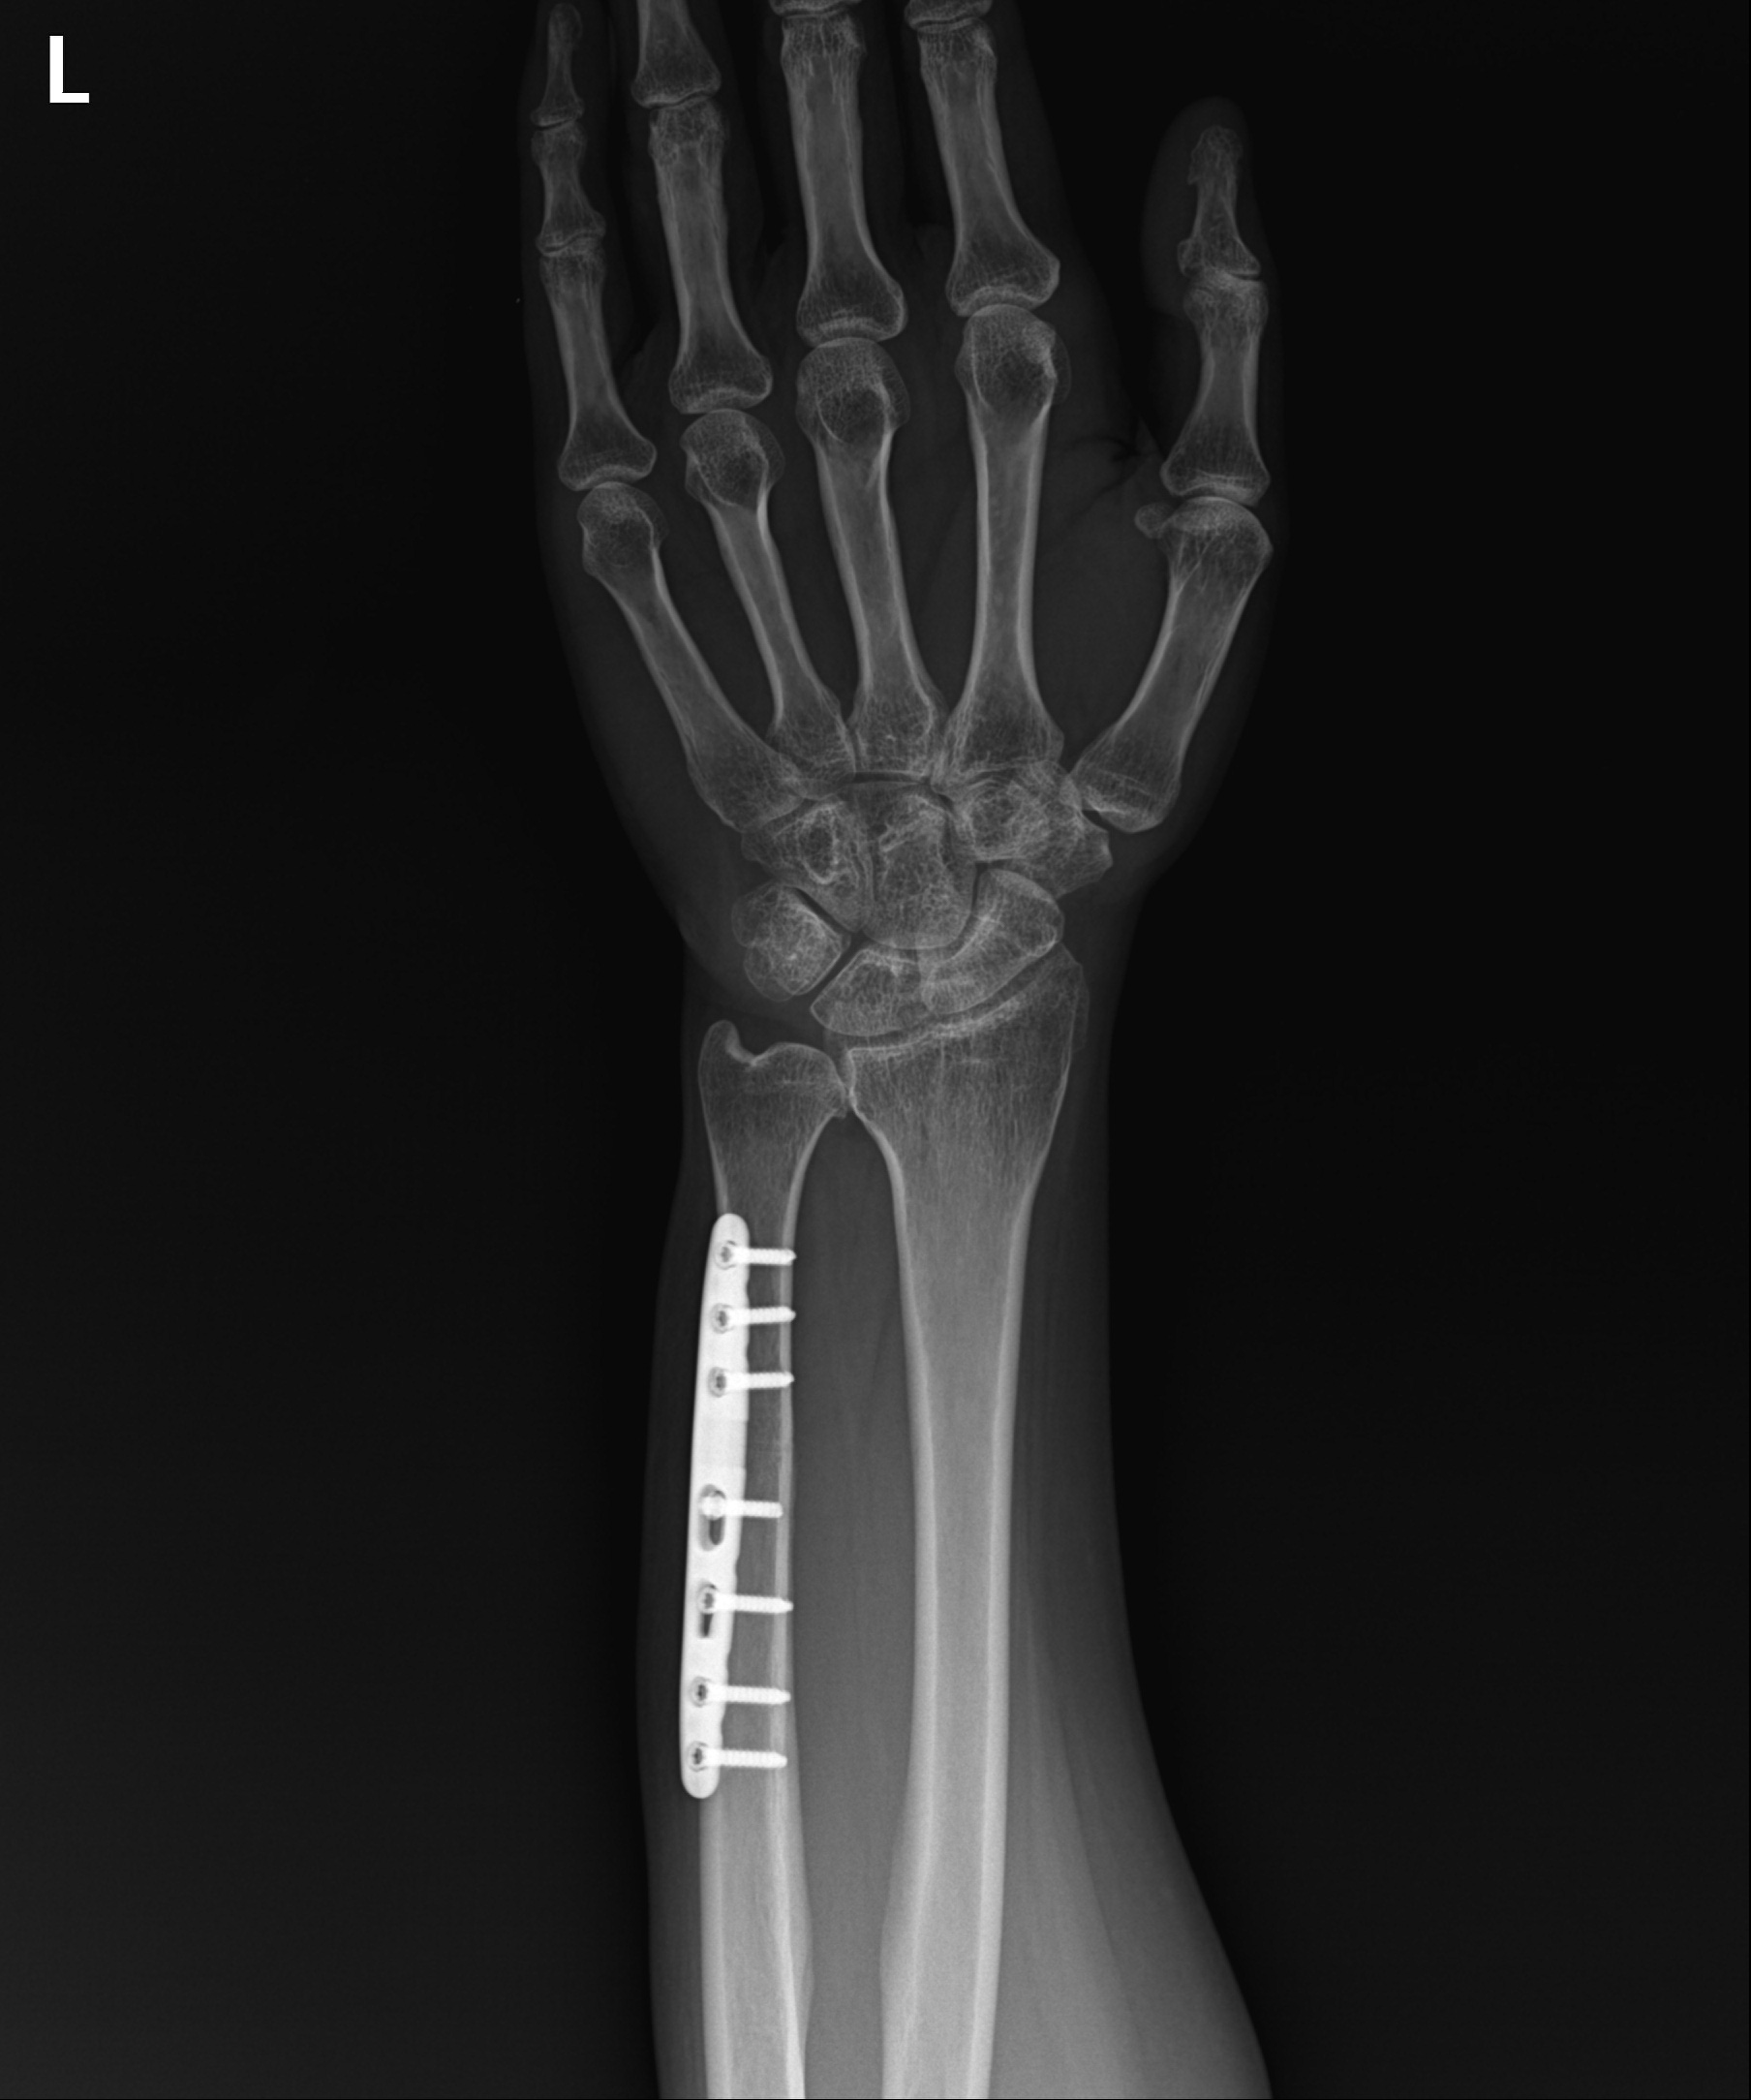

척골 단축술 1년 3개월 경과후

2023.03.06